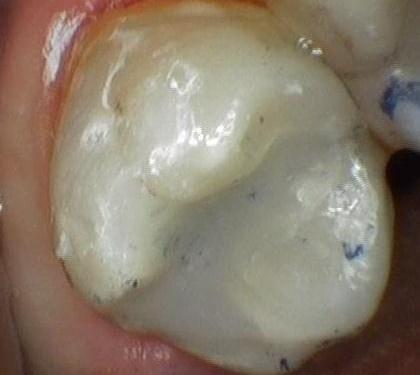

Tooth Colored Filling

This patient had an old metal filling that was starting to leak and had recurrent decay. There were also some cracks forming on the tooth. The filling was replaced with a new tooth-colored composite filling that will serve the patient well. The blue marks are from the paper used to check the bite and wash off.